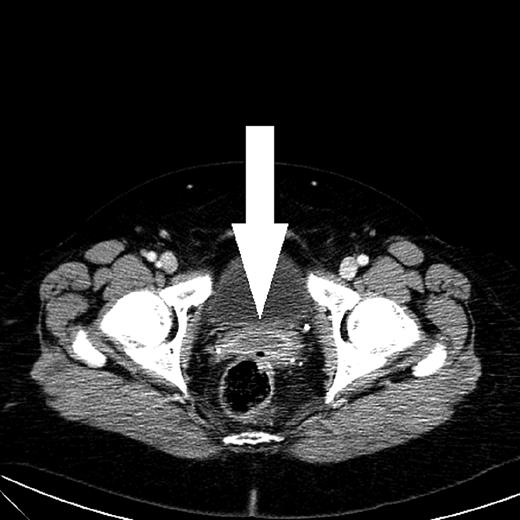

A computed tomography (CT) scan showed a 2.7 cm wide abscess in the Douglas pouch (Fig. 1). Anoscopy showed no rectal communication or other anorectal pathology and the abscess was drained transvaginally. Microbiological testing was positive for Enterococcus faecalis.

CT scan shows an abscess with peripheral rim enhancement in the Douglas pouch.